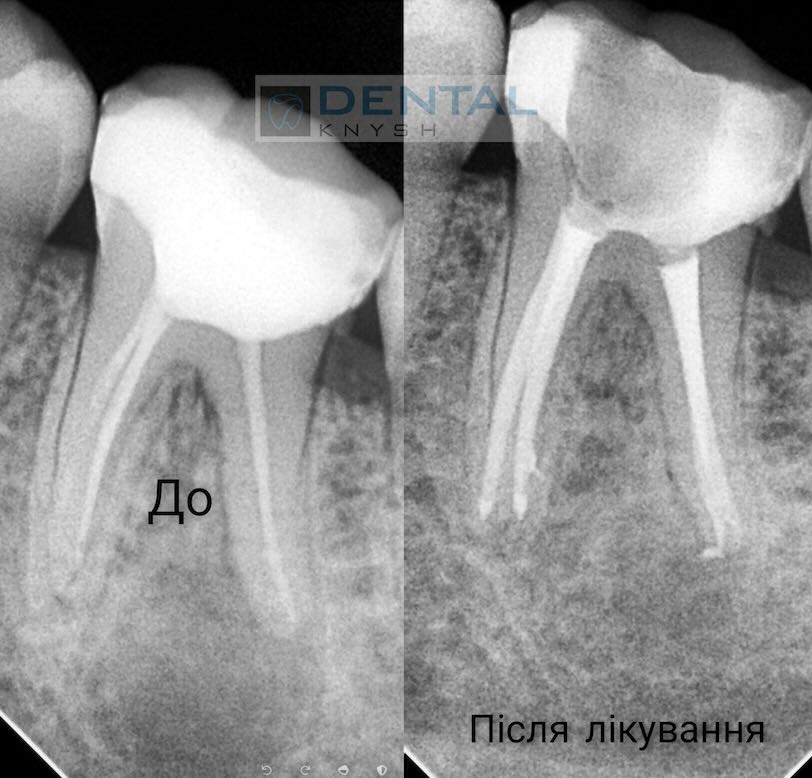

„Leczenie kanałowe pod mikroskopem daje najlepsze wyniki leczenia bez żadnych zastrzeżeń.

Nie każda klinika ma mikroskop do leczenia stomatologicznego, ale w przyszłości mikroskop będzie koniecznością. Im lepszy widok pola pracy, tym lepsze wyniki leczenia.

Początkowo fotele dentystyczne były w tym celu uzupełniane lampami, ale wraz z pojawieniem się mikroskopów stomatologia weszła w nowy etap rozwoju”.

Fotorelacje